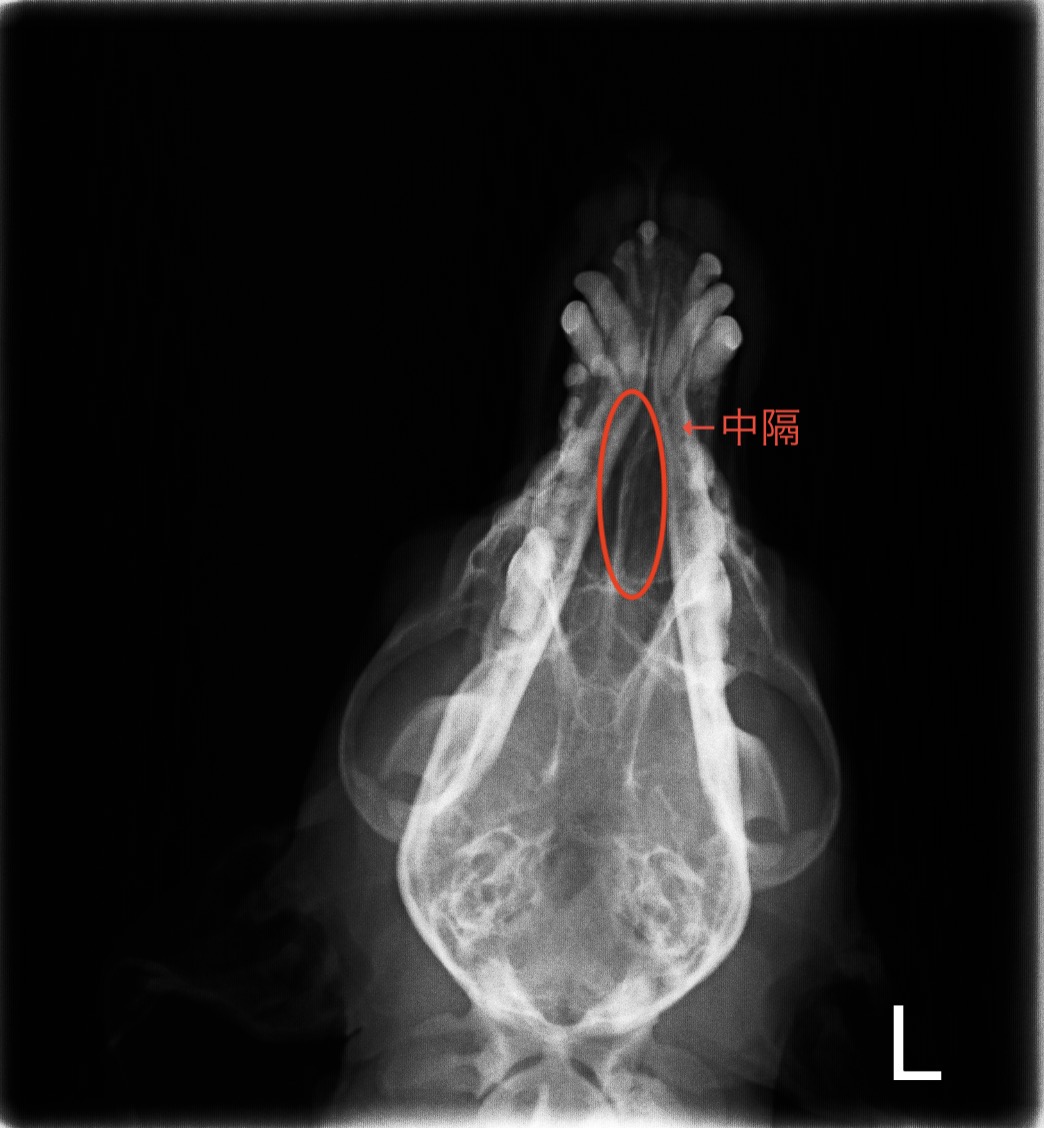

診断では画像検査が有用とされていますが、レントゲン検査では明らかな異常が写る場合が少ないため、

診断が困難な場合が多いのが現状です。

下の画像が院内での鼻部のレントゲン検査の画像です。

左右の鼻腔を隔てている中核が少し右側に圧迫されている様子は認められますが、鼻腔内に明らかな腫瘤は確認できませんでした。

左の鼻腔内に綿棒を入れて細胞の検査をしたところ、悪性の細胞が認められたためCT検査を実施する流れとなりました。